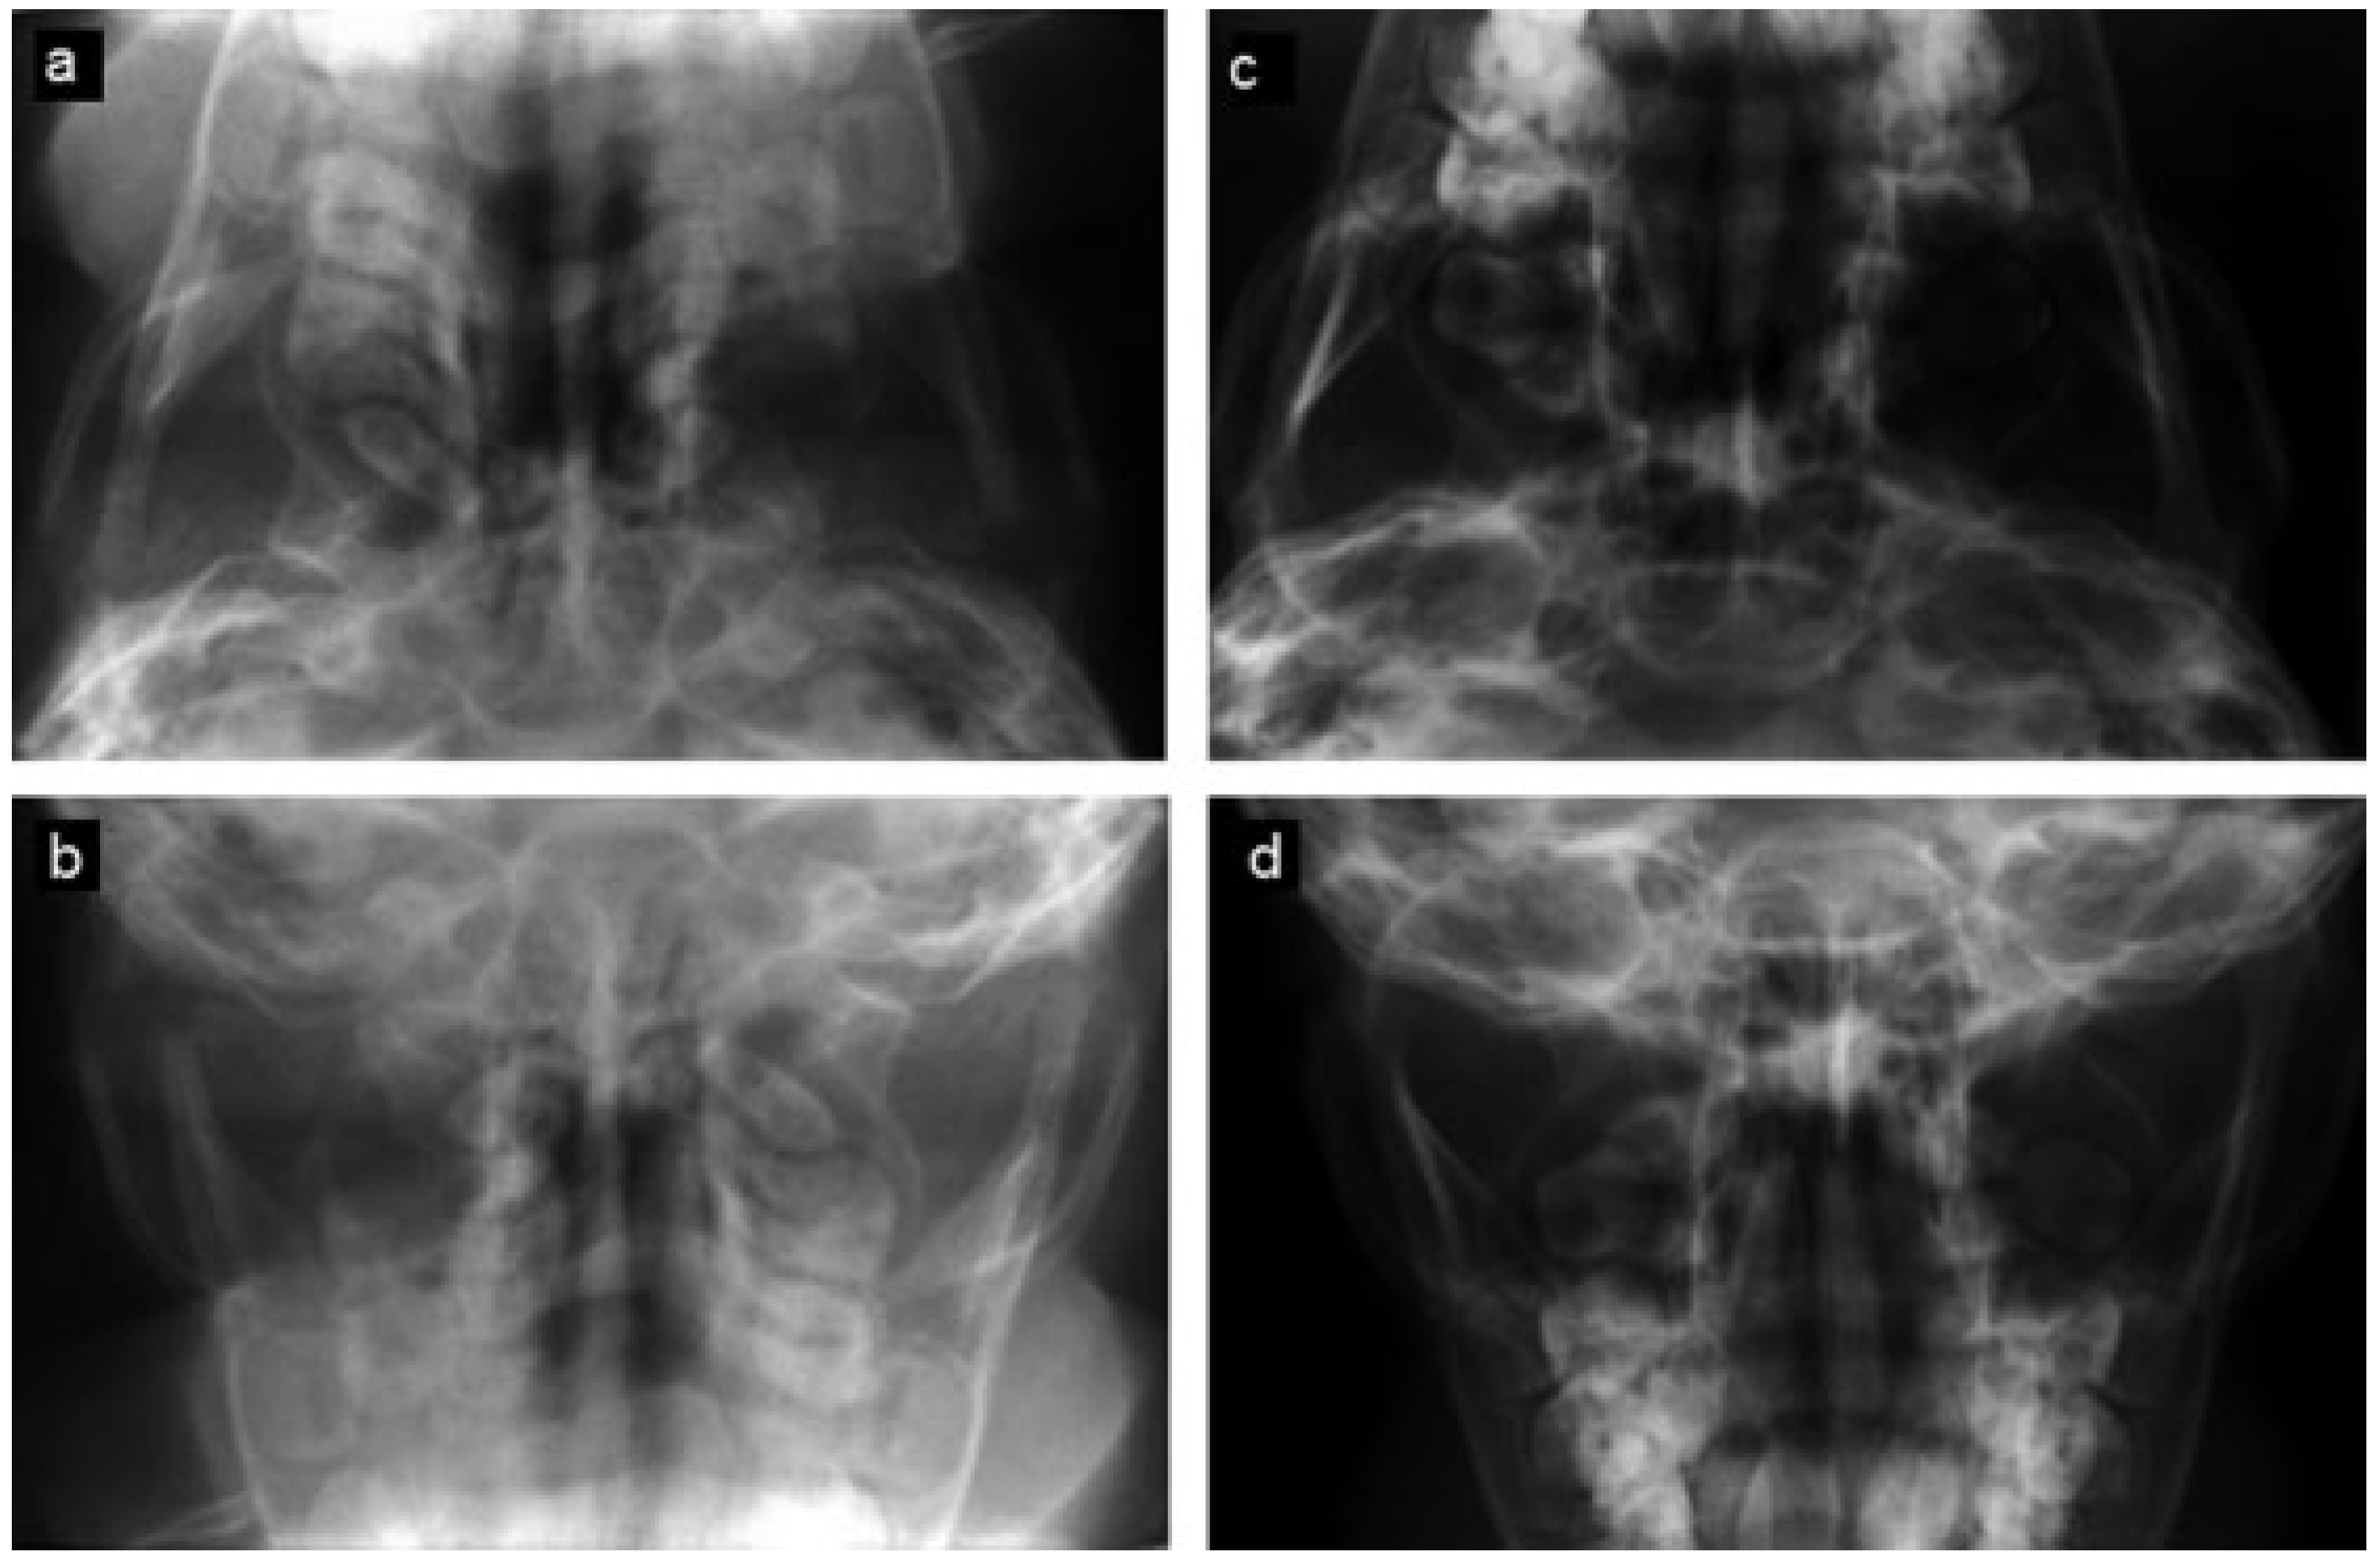

The third patient was an 18-month-old male patient who fell out of his crib and sustained bilateral subcondylar fractures and was allowed to continue bottle feedings and use of a pacifier. A Towne view radiograph documented normal condylar anatomy and position at age 5 (Figure 5). He returned at the age of 16 for third molar removal. At that time, he exhibited class I dental and skeletal occlusion and no history or physical findings of myofascial or TMJ symptoms.

Figure 5. (a,b) Comparison between pretreatment and (c,d) 3.5-year posttreatment axial and Towne view radiographs of patient 3 showing medially displaced right and minimally displaced left condylar fractures and well-healed and appropriately positioned condyles at follow-up.